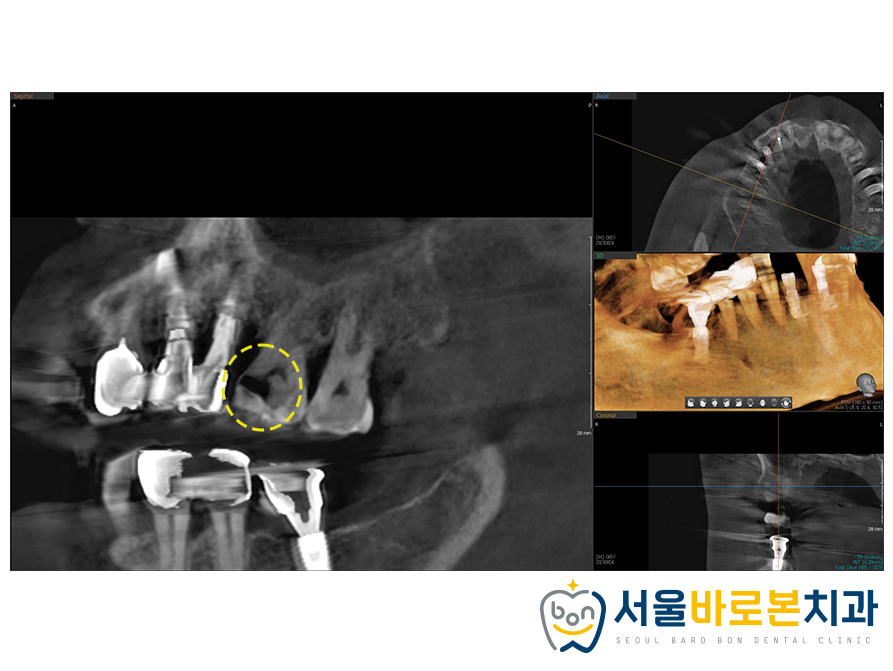

더욱 정밀한 체크를 위해 촬영한

3D-CT 사진을 보니

까맣게 비춰보이는 충치를

더욱 확연하게 체크할 수 있었습니다.

건강한 치아나 뼈가 있는 부분은

밀도가 높아 방사선이 투과하지 못해

하얗게 나온 것에 반면,

충치나 염증 등 좋지 않은 부위는

위와 같이 까맣게 나타납니다.

충치가 심하게 진행되어

치아 내부조직인 신경까지

충치가 감염된 상태였답니다.

환자분께서는 해당 치아를 발치하고

임플란트를 원하셨지만

자연치아를 살릴것을 권장드리고

치료 계획을 수립해보았답니다!